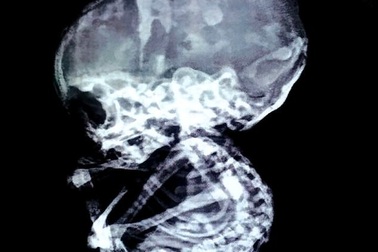

Sốc: Phát hiện bào thai trong bụng sau 15 năm bỏ thaiCác bác sĩ Ấn Độ đã vô cùng sốc khi phát hiện bệnh nhân 52 tuổi mang trong bụng khối thai suốt 15 năm qua.

Vụ cụ bà mang “thai đá”: Chưa xác định khối thai nằm ở đâu“Tui cũng không hiểu vì sao mà mình mang khối thai này, cho đến khi bị đau lưng rồi đi viện khám bệnh, bác sỹ nói tui mới biết”, cụ Sáu - người đàn bà đầu tiên tại Việt Nam mang “thai đá” tâm sự.

Cụ bà 76 tuổi mang “thai đá”: Mổ cấp cứu nếu khối thai gây biến chứngLiên quan đến trường hợp mang “thai đá” của cụ Sáu, các bác sỹ đầu ngành của tỉnh Khánh Hòa đã hội chẩn liên viện lần thứ 2 và thống nhất sẽ mổ cấp cứu trong trường hợp khối thai gây biến chứng.

Lưng đỡ đau, cụ bà mang “thai đá” được xuất việnLiên quan đến trường hợp “thai đá” của cụ Sáu, bác sỹ Nguyễn Hồng Quang, Giám đốc Bệnh viện Đa khoa Khu vực Cam Ranh (Khánh Hòa) cho biết bà cụ đã được xuất viện về nhà.

Hội chẩn liên viện trường hợp cụ bà mang “thai đá” gần 30 nămTrường hợp mang “thai đá” 30 năm của cụ Sáu dự kiến sẽ hội chẩn liên viện giữa bệnh viện Đa khoa Khánh Hòa với bệnh viện Đa khoa Khu vực Cam Ranh nhằm tìm hướng điều trị phù hợp vào ngày 31/3 này.